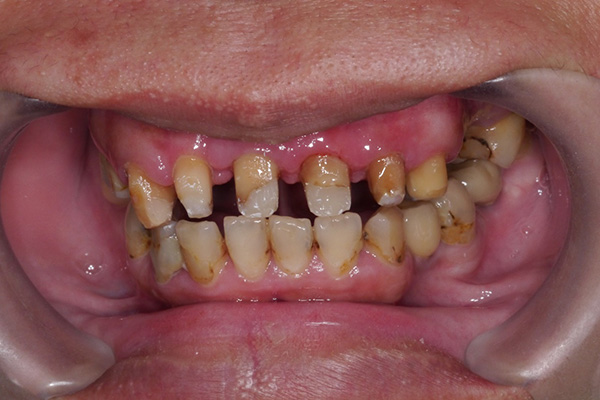

術後:牙冠加長,置入碳纖維釘柱後,裝上固定的臨時假牙,等待後植牙重建的同時,日常生活可擁有一定的美觀

![]() |

*以上醫師案例僅供參考;患者應依醫師個別評估結果為準。*

雄高信合美牙醫 牙周病科呂婷醫師 臨床手術案例提供